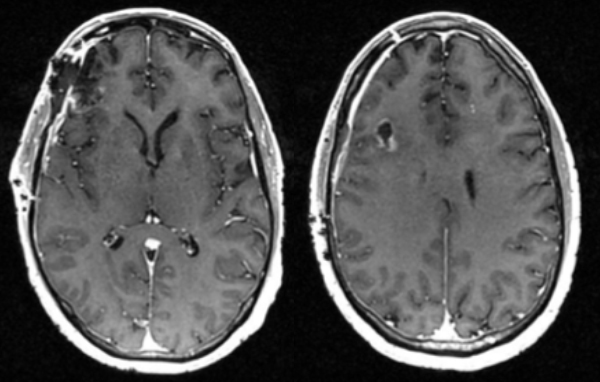

Pre-op

This is a 56-year-old man with a history of COPD and asthma who presented with a syncopal event and one week of retro-orbital headaches, blurry vision, and personality changes including apathy and disinhibition. He had a 40- pack-year smoking history but no prior malignancy. The exam revealed a pronator dri on the le upper extremity. MRI brain demonstrated 2 large right frontal heterogeneously enhancing masses with vasogenic edema causing midline shi and subfalcine herniation. The largest lesion was 3.9 x 4.0 cm on the inferior/sub frontal cortical surface, while the other was 3.0 x 2.7 cm in the superior subcortical frontal lobe. Further imaging showed a mediastinal mass suspicious for malignancy. He was started on Decadron for edema and Keppra for seizure prophylaxis.